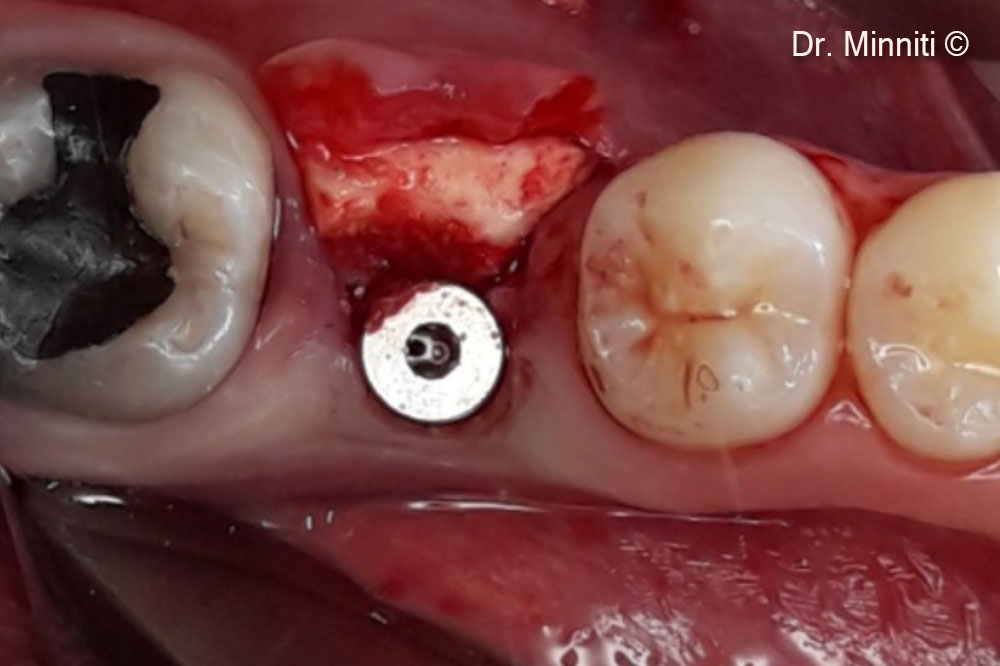

Vật liệu sinh học đã qua sử dụng

Derma

Derma